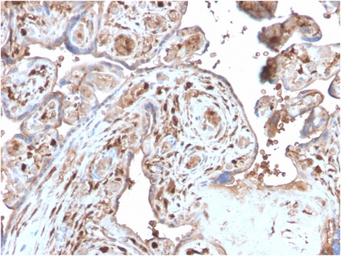

IHC-P analysis of human placenta tissue section using GTX02703 S100A4 antibody [S100A4/2750R].